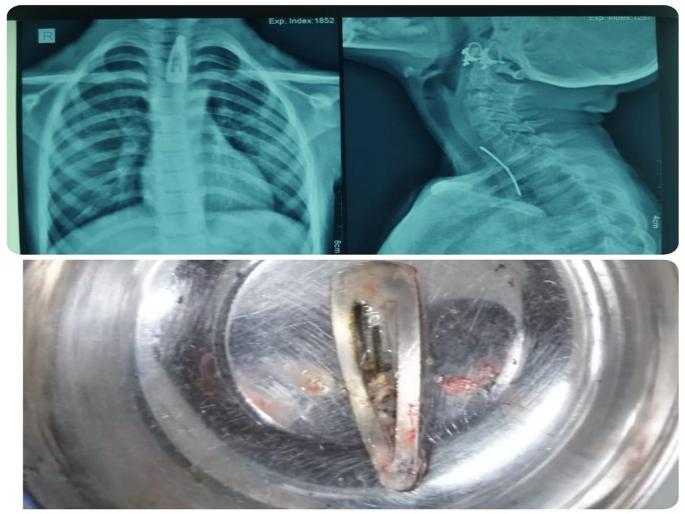

कोल्हापूर : बालिकेचे वय वर्षे अवघे सात. दोन दिवसांपूर्वी गिळताना त्रास होत असल्याने तिने आक्रोश मांडला होता. तिचे हाल पाहून आई-वडिलांनी तिला मंगळवारी (दि.४) मध्यरात्री सीपीआरमध्ये आणले. तिच्या छातीचा तसेच मानेची क्ष-किरण तपासणी केली असता तिच्या अन्ननलिकेत केसांत घालायची पिन अडकल्याचे दिसून आले. संभाव्य धोके लक्षात घेउन डॉक्टरांनी तत्काळ शस्त्रक्रिया करण्याचा निर्णय घेतला. भूल देऊन दुर्बिणीद्वारे त्याच पहाटे शस्त्रक्रिया करुन अन्ननलिकेत अडकलेली ही केसांची पिन काढली आणि या बालिकेला जीवदान दिले. शस्त्रक्रियेनंतर काल, बुधवारी तिला डिस्चार्ज देण्यात आला. तिची प्रकृती उत्तम असल्याचा निर्वाळा डॉक्टर लोकरे यांनी दिला.

पन्हाळा तालुक्यातील गरीब कुटूंबातील या बालिकेचे आई-वडील तिला मंगळवारी रात्री दोन वाजता सीपीआर मध्ये घेऊन आले. तिने दोन दिवसांपूर्वी केसांची ही पिन गिळली होती. तिच्या लक्षणांवरुन डॉक्टरांनी तिच्या छातीची तसेच मानेची एक्स-रे (क्ष-किरण) तपासणी केली, तेव्हा ती पिन अन्ननलिकेत अडकल्याचे आढळले. रुग्णांच्या नातेवाईकांनी या शस्त्रक्रियेची माहिती, तसेच संभाव्य धोके यांची कल्पना देउन पहाटे २.४५ वाजता राजर्षी शाहू महाराज शासकीय वैद्यकीय महाविद्यालय आणि सीपीआर (छत्रपती प्रमिलाराजे सर्वोपचार रुग्णालय) येथे हिरण्यकेशी इमारतीत कान, नाक, घसाशास्त्र विभागात दाखल केले.

दीड सेंटीमीटर होती पिन

या बालिकेच्या अन्ननलिकेत अडकलेल्या या केसांच्या पिनेची लांबी साधारण १.५ सेंटीमीटर होती. दोन दिवस ती अन्ननलिकेत अडकून पडल्यामुळे अन्ननलिकेला छिद्र पडण्याचा मोठा धोका निर्माण झाला होता. परंतु वेळीच अचून निदान झाल्यामुळे हे संभाव्य धोके टाळण्यात डॉक्टरांच्या टीमला यश आले. ही अत्यंत गुंतागुंतीची आणि जोखमीची शस्त्रक्रिया डॉक्टरांनी कुशलपणे पार पाडली.